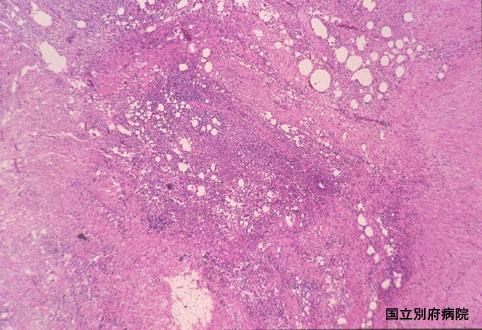

潰瘍部の弱拡大像です。結腸壁全体に著名な炎症細胞浸潤があり、壁の構築は破壊されています。

疾患(病理主体)の分類炎症性・潰瘍性疾患/虚血性腸炎

部位(臓器別)大腸/上行

検査方法ミクロ